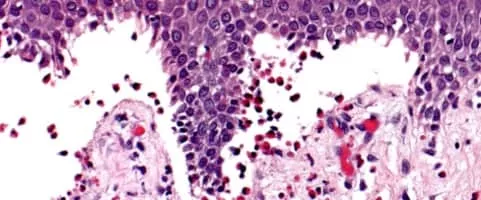

Dermatopathology photograph

Dermatopathology is a joint subspecialty of dermatology and pathology or surgical pathology that focuses on the study of cutaneous diseases at a microscopic and molecular level. It also encompasses analyses of the potential causes of skin diseases at a basic level.